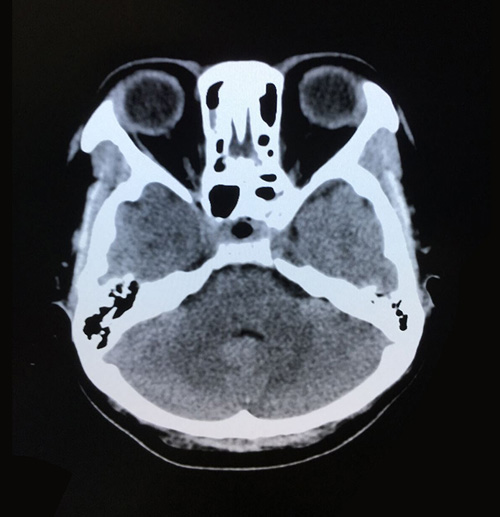

术后影像:两侧大脑,小脑及脑干形态如常,脑沟脑池未见异常